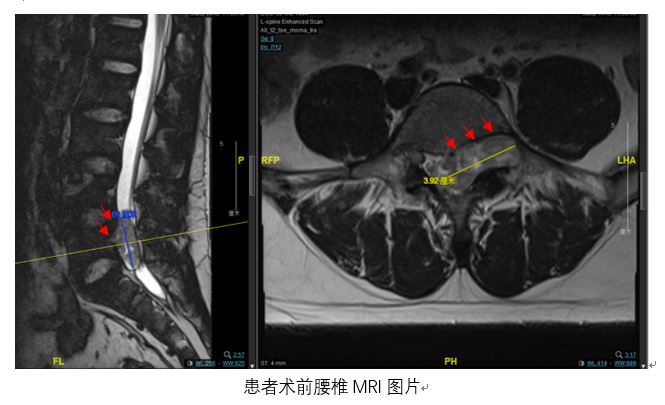

腰椎MRI检查结果显示,小陈腰骶部椎管内有一个呈哑铃型异常占位,占据了左侧椎间孔且破坏到椎体骨质,凭借丰富临床经验,赵杰主任诊断意见为椎管内神经鞘瘤,需尽快手术。

术后影像学提示患者关节突关节等骨性结构完整,术后病理回报肿瘤切缘干净,肿瘤切除彻底。患者腰腿痛症状明显改善,足部麻木感缓解。